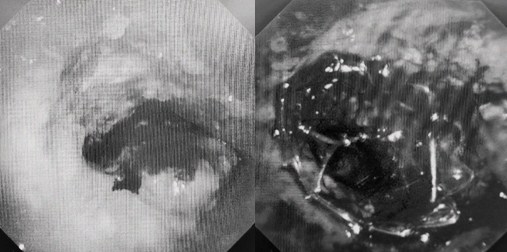

患者入院第二天,在麻醉手術(shù)中心全力配合下,歐陽海峰帶領(lǐng)呼吸介入團(tuán)隊(duì),歷時(shí)40分鐘快速置入硬質(zhì)支氣管鏡、鏟切腫瘤,并順利植入全覆膜TTS支氣管金屬支架。患者氣短癥狀即刻緩解,為患者贏得了寶貴的后續(xù)治療機(jī)會(huì)。